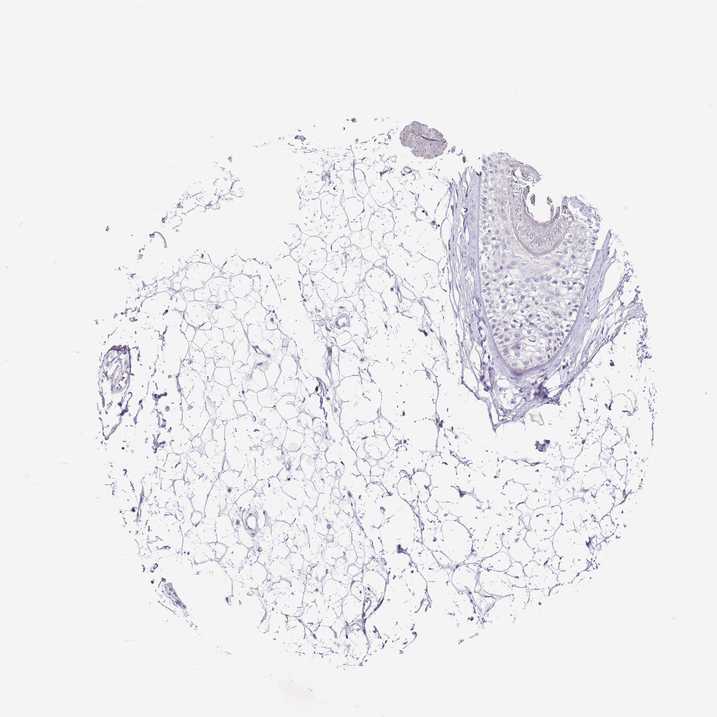

SKIN 1 - Antibody stainingi

Antibody staining in the annotated cell types in the current human tissue is reported as not detected, low, medium, or high, based on conventional immunohistochemistry profiling in selected tissues. This score is based on the combination of the staining intensity and fraction of stained cells.

Each image is clickable and will lead to virtual microscopy that enables deeper exploration of all samples and also displays staining intensity scores, fraction scores and subcellular localization as well as patient and tissue information for each sample.

Antibody HPA023364

Langerhans Low

Fibroblasts Not detected

Keratinocytes Low

Melanocytes Not detected